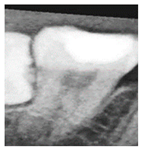

Two common segmentation approaches exist, with one involving the masking of the target tooth to exclude non-relevant areas, while the other segments the teeth based on their individual contours [24,25]. However, because the identification of impacted teeth requires the contextual presence of at least two adjacent teeth, both segmentation methods were modified accordingly in this study. Through empirical evaluation and implementation, a frame size of pixels was determined to be the most effective for capturing a sufficient diagnostic region, as shown in Figure 9.

Figure 9.

An example of a image cropped from a PANO image.